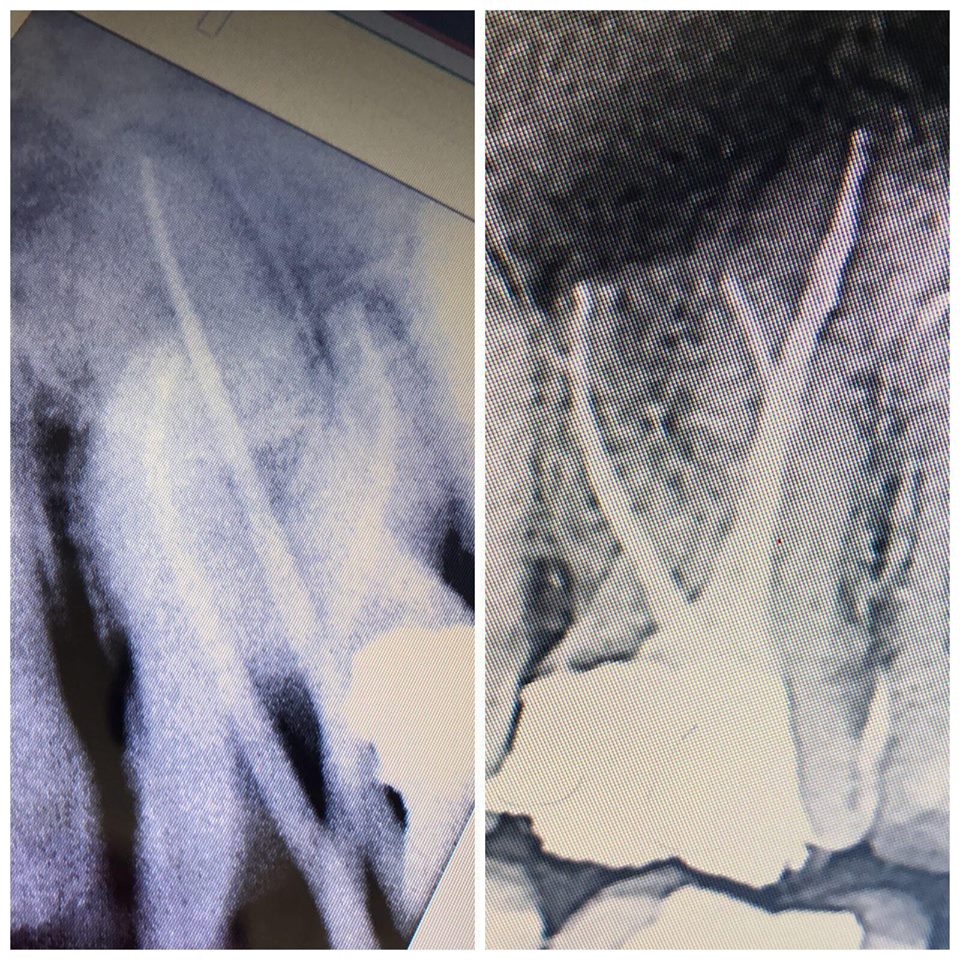

KANAL TEDAVİSİ VE DOLGU